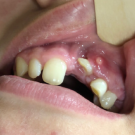

A 14-year-old girl presented with an ongoing problem with dental crowding in the area of the upper central incisors; a previous CT scan of the head had identified a cyst emanating from the area of the...

12/27/2020